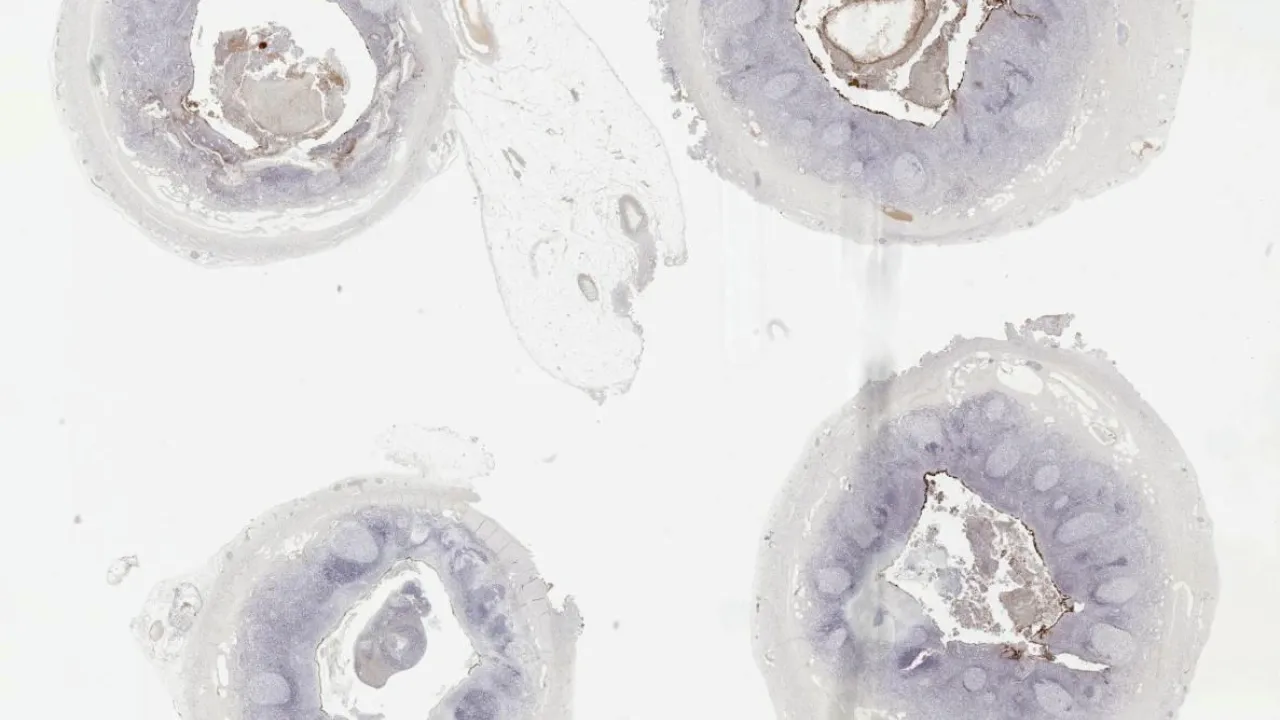

Small intestine, Systemic Mastocytosis, CD117 stain

Small intestine, Systemic Mastocytosis, CD68 stain

Small intestine, Systemic mastocytosis, H&E stain